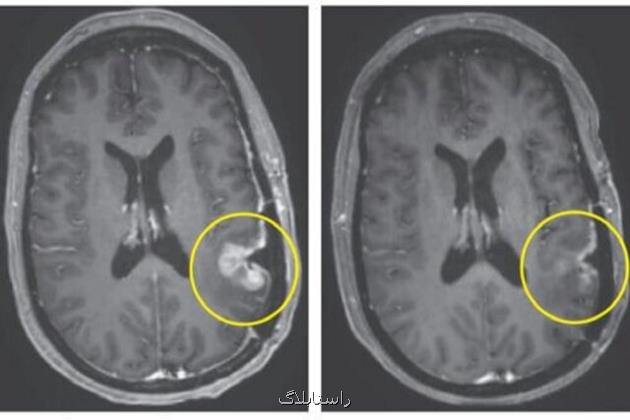

قابل توجه است که تنها چند روز بعد از درمان، بیماران شاهد کاهش قابل توجهی در تومورهای خود بودند، به صورتی که یک بیمار در عرض پنج روز به پسرفت حدودا کامل تومور دست یافت.

یکی از بیماران، مردی ۷۲ ساله بودکه شاهد کاهش بیشتر از ۶۰ درصدی تومور خود بود که به مدت شش ماه ادامه داشت، در حالیکه یک زن ۵۷ ساله تنها پنج روز بعد از یک تزریق، حدودا پسرفت کامل تومور داشت.